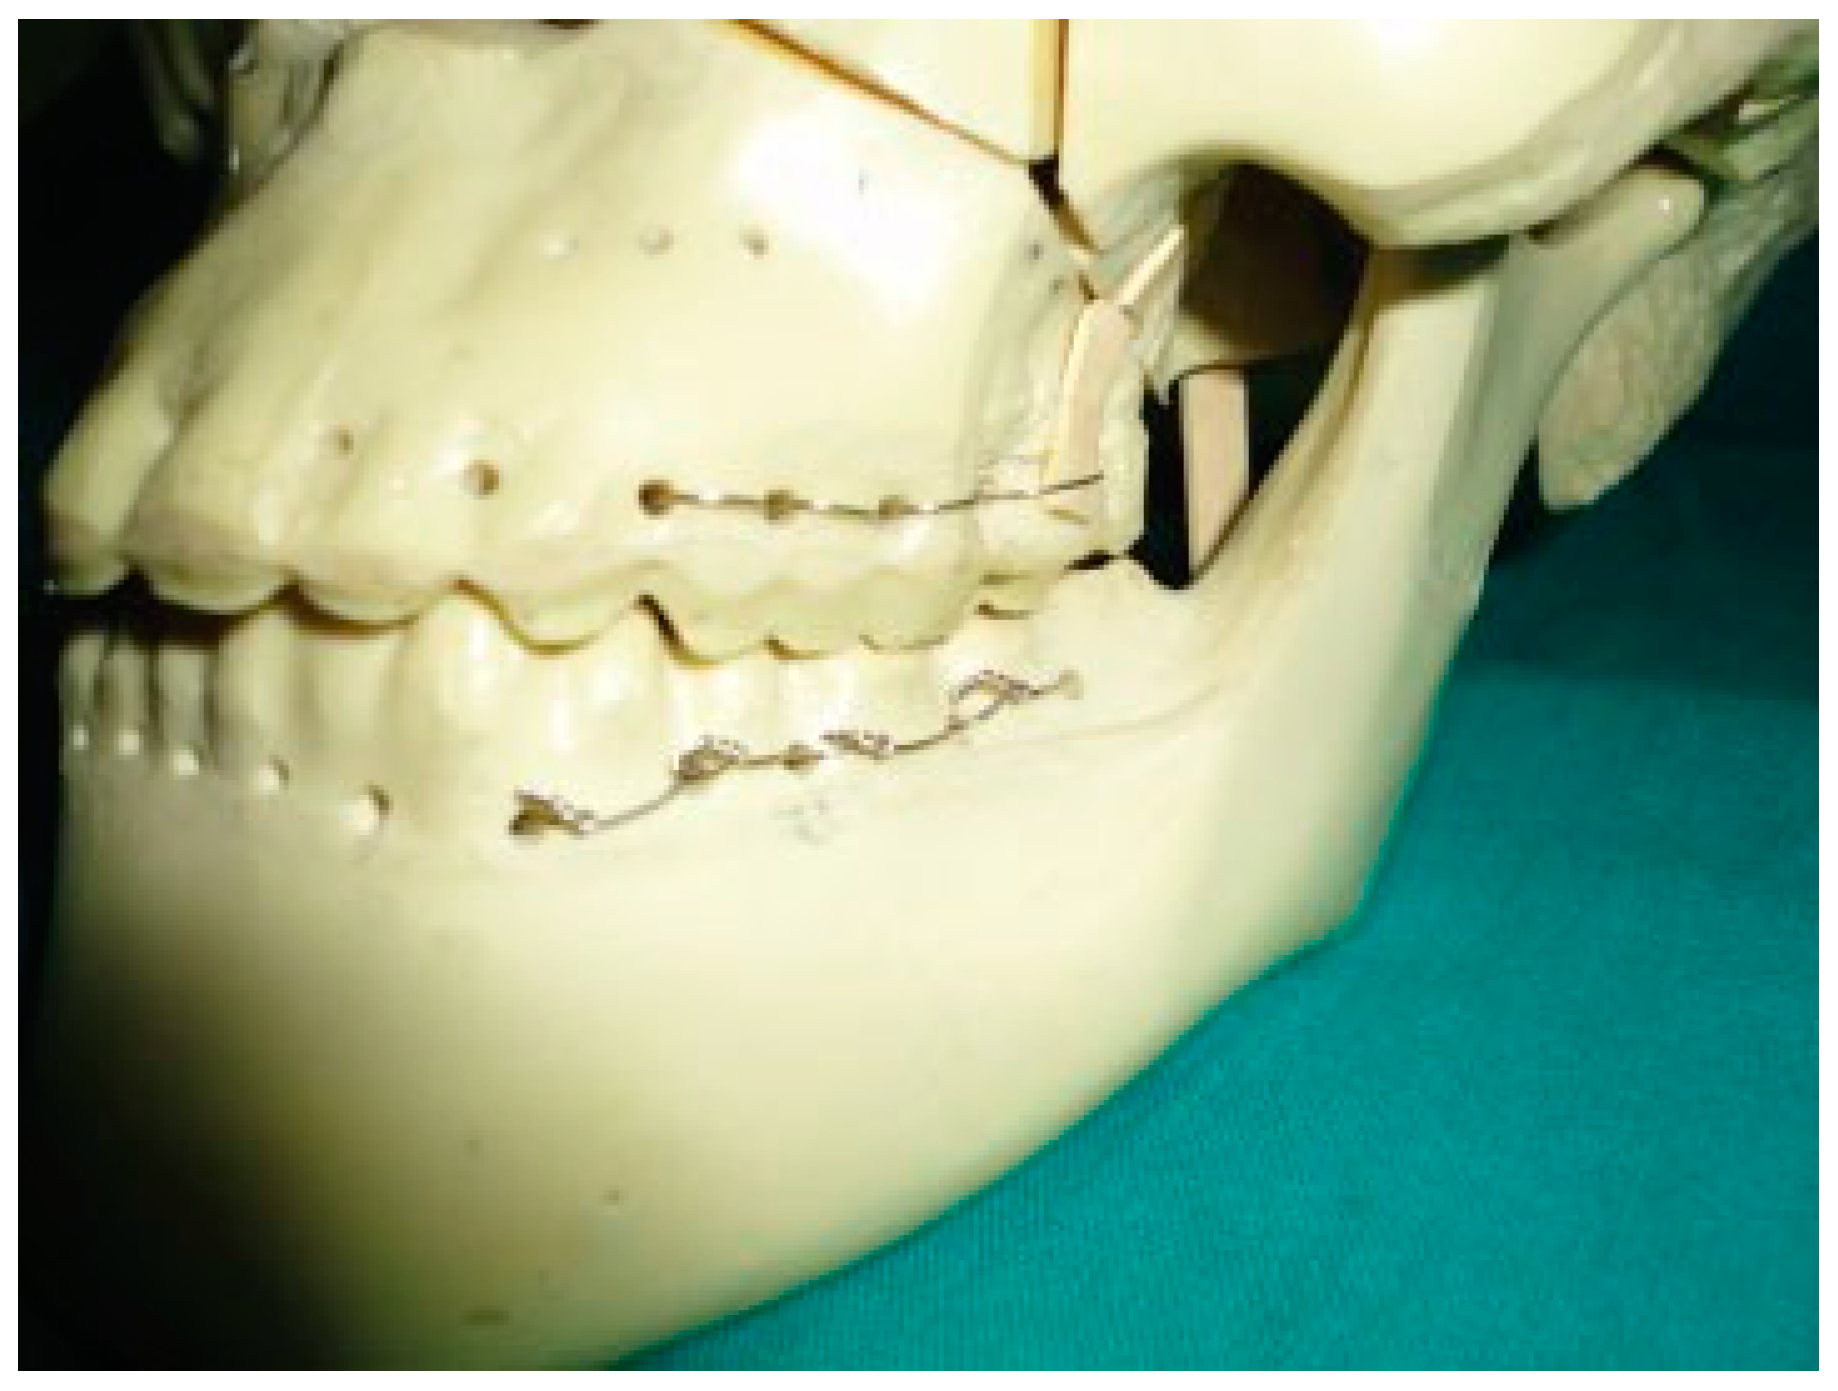

Figure 3. Step 2 of the technique.

In this technique, a wire is passed around the neck of the upper first molar tooth; both ends of the wire go from buccal to palatal, one along the mesial surface and other end along the distal surface of tooth above the maxillary contact (Figure 2). Then both ends of the wire are passed back around the lower first molar from lingual to buccal aspect in a similar manner below the mandibular contact (Figure 3). A similar procedure is repeated on the second molar and premolar teeth and on the contralateral side (molar and premolar region). After achieving the occlusion, the ends of the wire are twisted together on the buccal surface of the lower premolar and molar teeth on both sides (Figure 4, Figure 5 and Figure 6). At the end of treatment, wires can be easily removed with minimal trauma to patient.